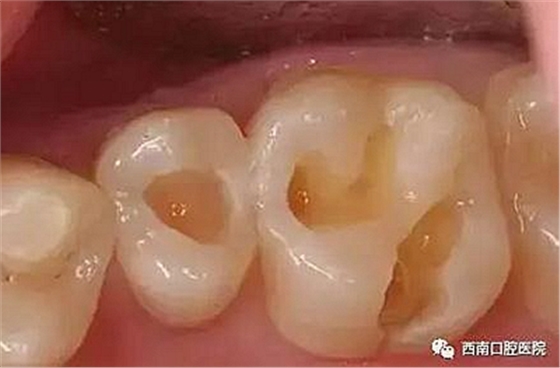

小齲洞可能不會引起疼痛

未必會引起患者注意

較大的齲洞就會因殘留食物的細菌

和冷、熱、酸、甜食物的刺激

引起牙疼了

我們來看下各個材料充填之后的顏值吧!